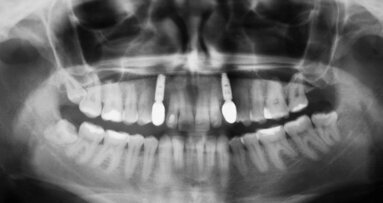

Pacjent zgłosił się w dniu urazu. W jego wyniku złamany został korzeń siekacza przyśrodkowego prawego (Ryc. 1-3). Z powodu dużego lęku przed zabiegami z zakresu chirurgii jamy ustnej, pacjent odstąpił od proponowanej ekstrakcji złamanego zęba z jednoczesnym zabiegiem augmentacji i regeneracji kości przed przyszłą implantacją. W związku z tym jedynie usunięto ząb wraz ze złamanym korzeniem i zabezpieczono ujście zębodołu za pomocą mostu adhezyjnego z przęsłem wykonanym z korony utraconego zęba. (Ryc. 4-5).

Po upływie ok. 7 miesięcy pacjent ponownie pojawił się w klinice celem kontroli, zgłaszał też dyskretne dolegliwości ze strony siekaczy górnych po stornie lewej (Ryc. 6). Wyraził gotowość do zabiegu implantacji, jednakże całkowicie odmówił wykonywania dodatkowych procedur, takich jak augmentacja lub regeneracja kości oraz przeszczep tkanki łącznej z podniebienia celem augmentacji od strony przedsionka. Lęk pacjenta budził konieczność wytworzenia rany-dawcy tkanki przeszczepianej. Nadmienić warto, iż zęby sieczne w szczęce lewej wyleczono endodontycznie i wspomniane dolegliwości ustąpiły.

Z powodu widocznego ubytku w wymiarze wargowo-podniebiennym od strony przedsionka w projekcji brakującego zęba siecznego prawego przyśrodkowego (Ryc. 6-8) pacjent wyraził zgodę jedynie na augmentację z użyciem błon kolagenowych.

Uwzględniając zgodę pacjenta na jeden tylko zabieg, zastosowano procedurę jednoetapową. Wszczepiono implant o średnicy platformy 4 mm, co widać po oznaczeniu na śrubie gojącej umocowanej jedynie na krótki czas w trakcie zabiegu (Ryc. 12). W czasie, gdy śruba gojąca utrzymywała kontur tkanek miękkich, wykonano płat dzielony, pozostawiając okostną w nienaruszonym stanie (Ryc. 12) i w tak stworzoną kieszeń włożono 4 płatki błony Osseoguard. Wielowarstwowe jej ułożenie generuje bliznę między okostną a błoną śluzową. Blizna jest „wieczna” i jej objętość jest przez wiele lat prawie niezmienna. Z powodu sztywności błony OsseoGuard zaleca się obcięcie lub zaokrąglenie jej rogów, aby nie traumatyzowały błony śluzowej i nie powodowały jej perforacji.